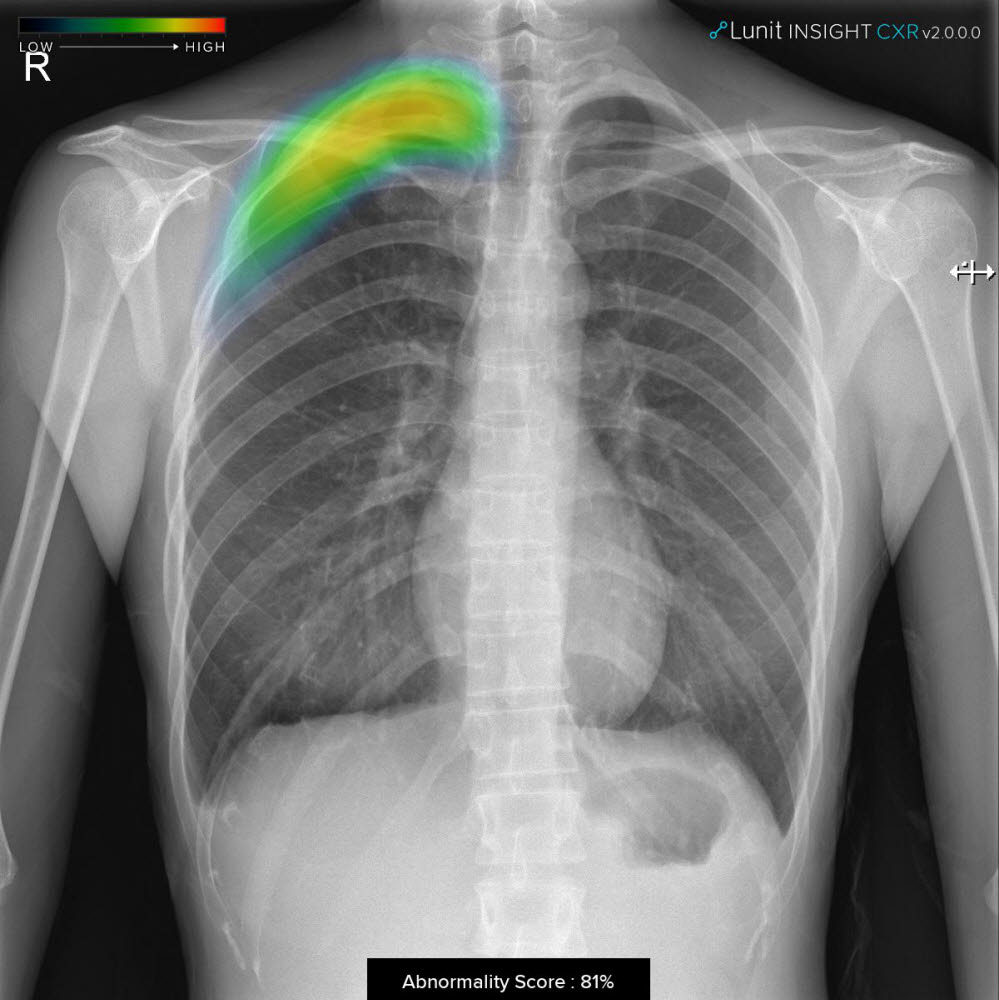

루닛은 AI로 암 등을 진단하는 솔루션을 개발하고 있다. 이번 달 유방암 진단보조 솔루션 '루닛 인사이트 MMG'가 미국 식품의약국(FDA) 승인을 받았다.